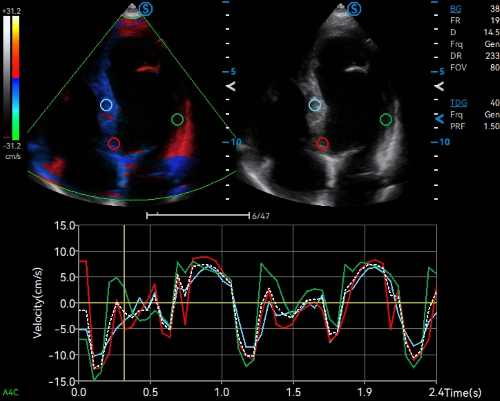

- Category: Color Doppler